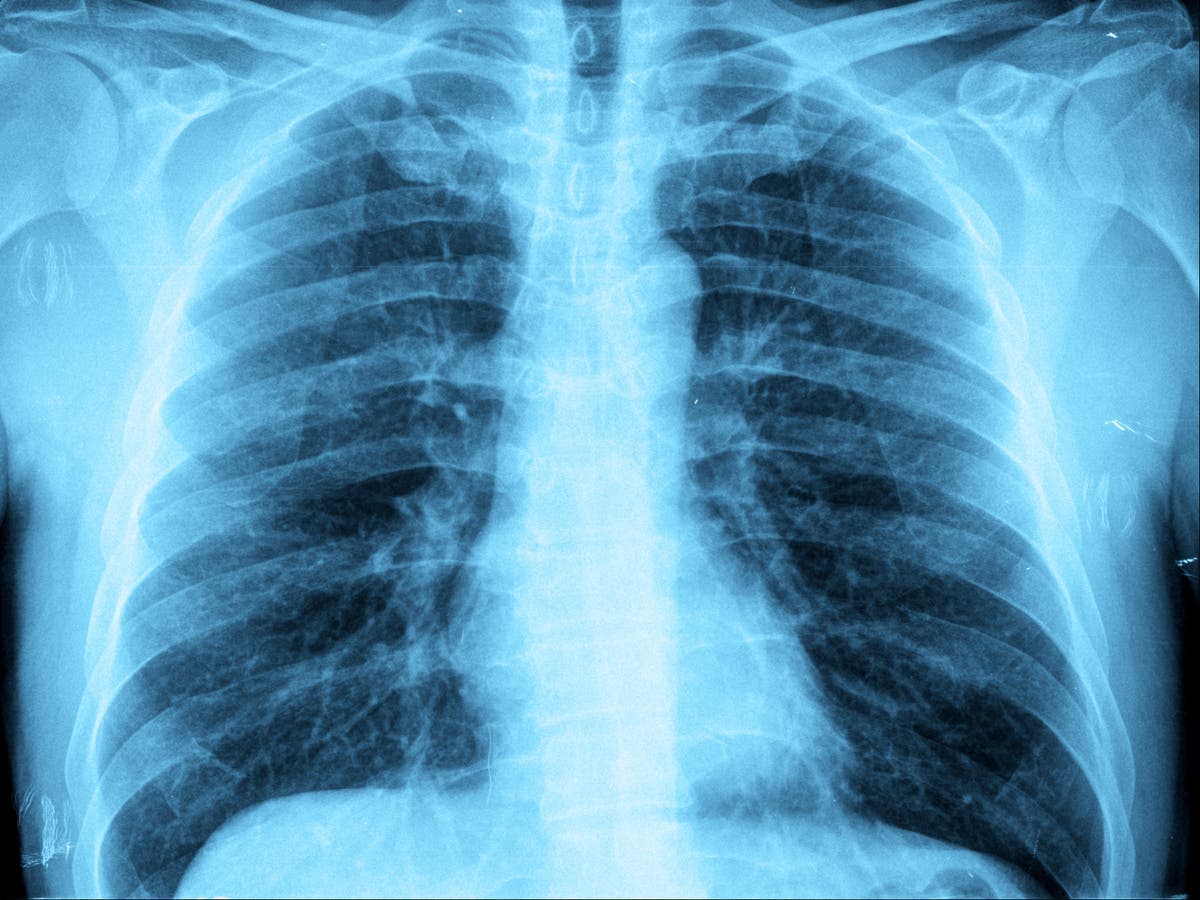

Doctors in China suspect that the recent 'white lung' pneumonia outbreak, which primarily affected children, may have been driven by antibiotic-resistant infections known as superbugs. Tests have revealed a surge in mycoplasma pneumoniae infections, a bacteria that can trigger pneumonia, with 90% of cases in China now resistant to common antibiotics. Overprescription and overuse of antibiotics, as well as the practice of administering antibiotics via intravenous drips, have contributed to the rise of antibiotic resistance. The outbreak in China, characterized by white patches on X-rays of the lungs, has prompted concerns about the lack of effective treatments for children and the need to curb antibiotic drug resistance.